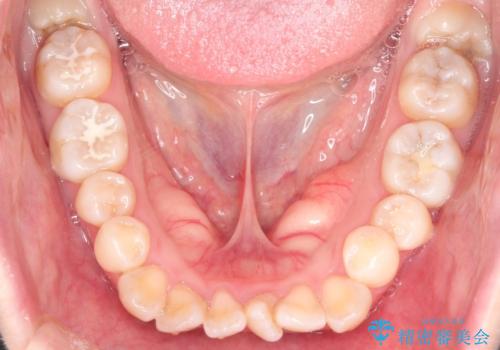

- ”口元を下げたい”が主訴で来院されました。

抜歯してワイヤー矯正を行い、口元も改善され大変満足していただきました。

小臼歯の抜歯を行うことで口元を改善することができました。